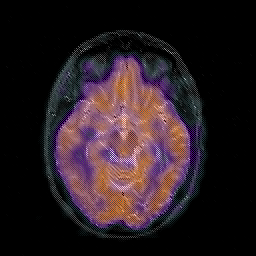

Glioblastoma multiforme overlay -- Slice #23

[Home][Help][Clinical][Tour 1][Tour 2][Tour 3] Slice 23